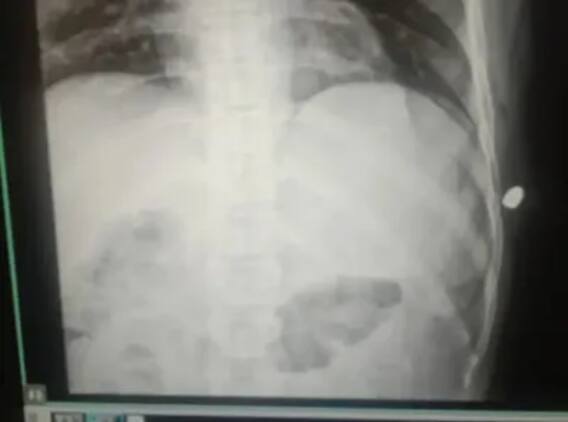

உடனே சந்த் அருகில் சென்று பார்த்த போது அவருக்கு ஏற்பட்டு இருக்கும் பூனை கீறல் அல்ல, அது துப்பாக்கிச் சூடு காயம் என்பதை உணர்ந்தார். உடனே சந்த்தை அவர் எழுப்பி அருகில் உள்ள மருத்துவமனைக்குச் அழைத்து சென்றார். அங்கு மருத்துவர்கள் சந்த்தை எக்ஸ்ரே ஸ்கேன் செய்தனர்.

அப்போது அவரது உடலில் தோட்டா இருந்தது தெரிய வந்தது. தோட்டா சிக்கியதால் சந்த்தின், முக்கிய உறுப்புகள் கடுமையாக பதிக்கப்பட்டது. இதனையொட்டி சந்த்திற்கு, பொது மயக்க மருந்துகளின் கீழ் அறுவை சிகிச்சைக்கு உட்படுத்தப்பட்டது. பிறகு செப்டம்பர் 17 ஆம் தேதி காலை மருத்துவர்கள் அறுவை சிகிச்சை செய்து தோட்டாவை அகற்றினர். மருத்துவமனையில் எலும்பியல் அறுவை சிகிச்சை நிபுணர்கள் நரசீரம் மற்றும் வர்தராம் தேவாசி வெற்றிகரமாக அறுவை சிகிச்சை செய்தனர். சந்த் புல்லட் காயத்தில் இருந்து முழுமையாக குணமடைவார் என்று எதிர்பார்க்கப்படுகிறது.